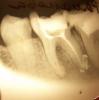

charity Опубликовано 30 июля, 2010 Поделиться Опубликовано 30 июля, 2010 (изменено) Здравствуйте! 36му зубу был поставлен диагноз "хронический гранулематозный периодонтит". Был сделан снимок до лечения. Зуб был открыт, неделю полоскала раствором соды-соли-йода, затем была заложена паста vitapex и снова сделан снимок. Посмотрите, пожалуйста, снимки и развейте или подтвердите мои опасения. Кажется, на снимке после закладки пасты видно, что сломана верхушка корня. Если да, чем это грозит? Изменено 30 июля, 2010 пользователем charity Ссылка на комментарий

charity Опубликовано 30 июля, 2010 Автор Поделиться Опубликовано 30 июля, 2010 Вставила более четкий сегодняшний снимок. Так какие будут последствия для здоровья, если зуб не удалить? Ссылка на комментарий

Мартовский Опубликовано 30 июля, 2010 Поделиться Опубликовано 30 июля, 2010 Вставила более четкий сегодняшний снимок. Так какие будут последствия для здоровья, если зуб не удалить?Никакой поломки верхушки я не вижу. Всё что видно, это паста, вышедшая за неё. Каналы пролечить, поставить коронку. Возможен вполне благоприятный исход. Ссылка на комментарий

Henny Опубликовано 30 июля, 2010 Поделиться Опубликовано 30 июля, 2010 Вставила более четкий сегодняшний снимок. Так какие будут последствия для здоровья, если зуб не удалить?на более четком и впрямь не та картина ,что на предыдущем,на зуб нормально накусывайте,боли есть?и верните еще раз другой снимок Ссылка на комментарий